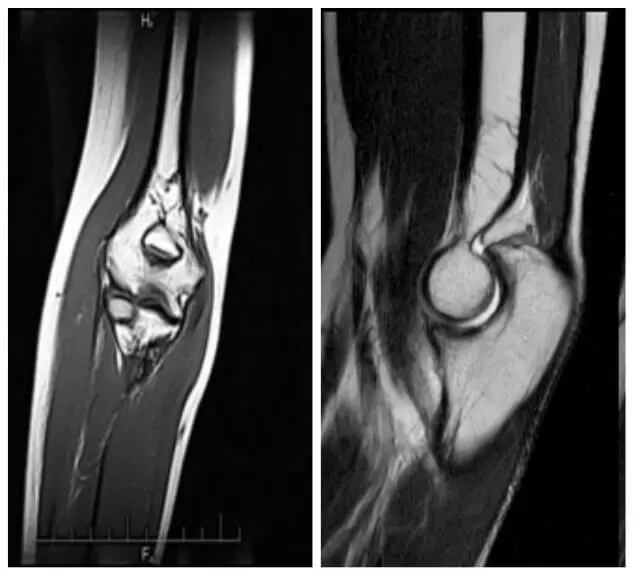

МРТ колінного суглоба

МРТ коліна дозволяє побачити такі зміни, як розрив або розшарування меніска, розрив або надрив (травму) зв’язок, травму хряща, запалення кістки і в підхрящевій пластині, запалення жирового тіла Гоффа та ін. МРТ колінного суглоба дозволяє побачити артрит (накопичення рідини в колінному суглобі).

Артроз при МРТ видно, але частіше для цього використовують рентген зважаючи на більшу інформативність при діагностиці артрозу коліна. Читати більше про показання, протипоказання і що можна обстежити в колінному суглобі.

МРТ ліктьового суглоба

Ліктьовий суглоб, як і гомілковостопний, має складну будову, оскільки формується з трьох кісток: плечової, ліктьової і променевої.

Для повноцінного дослідження проводять огляд, клінічне тестування. Ці дослідження проводить лікар ортопед-травматолог або ревматолог . Після чого проводять МРТ ліктьового суглоба. Але, перед МРТ дослідженням потрібно провести рентген ліктьового суглоба . Особливо при його травмі.

Читати докладніше про МРТ ліктьового суглоба .